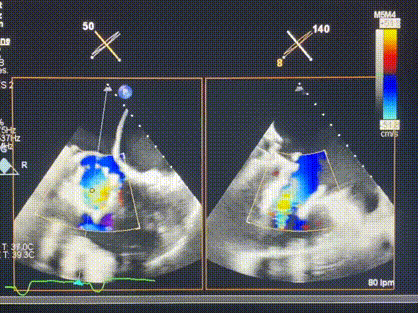

術(shù)后超聲顯示僅殘余微量瓣周漏

LuX-Valve Plus經(jīng)血管三尖瓣置換系統(tǒng)此次“出海”圓滿完成,術(shù)后Rodrigo Estévez-Loureiro教授對(duì)LuX-Valve Plus經(jīng)血管三尖瓣置換系統(tǒng)的器械性能和治療效果大為稱贊,認(rèn)為LuX-Valve Plus的手術(shù)體驗(yàn)非常好。術(shù)后即刻超聲顯示三尖瓣反流幾乎完全消失,血流動(dòng)力學(xué)改善顯著,患者恢復(fù)快。在面對(duì)復(fù)雜解剖結(jié)構(gòu)、超聲影像質(zhì)量不佳、有起搏導(dǎo)線干擾時(shí),Lux-Valve Plus也體現(xiàn)了極強(qiáng)的適應(yīng)性。Thomas Modine教授和Anson Cheung教授也肯定了LuX-Valve Plus術(shù)中操作的便捷性,認(rèn)為LuX-Valve Plus容錯(cuò)率高,對(duì)術(shù)中影像的依賴較小,后期希望可以更多的應(yīng)用LuX-Valve Plus三尖瓣置換系統(tǒng)于臨床實(shí)踐,讓更多的三尖瓣重度反流患者盡早獲益,改善預(yù)后。